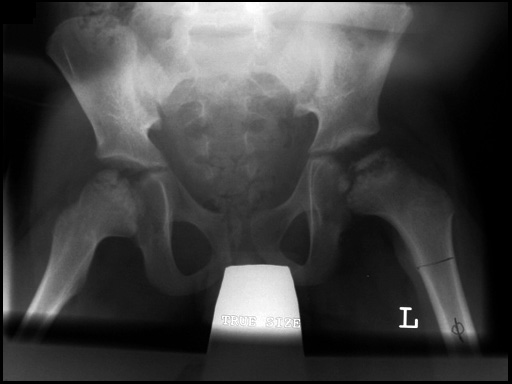

Case 1:

6-year-old boy with Legg-Calv-Perthes disease.